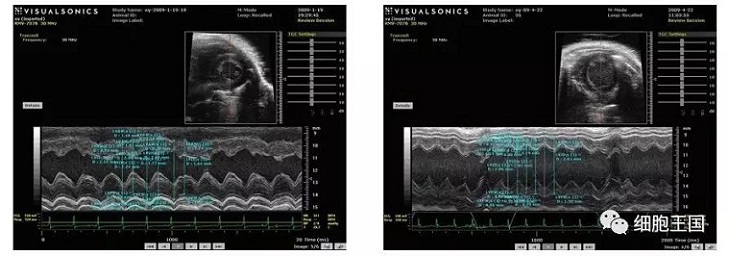

2010年暨南大學(xué)醫(yī)學(xué)院血液病研究所李軍研究小組,在間充質(zhì)干細(xì)胞抗衰老作用的動(dòng)物實(shí)驗(yàn)中發(fā)現(xiàn),干細(xì)胞移植組存活日期明顯長(zhǎng)于對(duì)照組,移植3個(gè)月后評(píng)價(jià)心功能的指標(biāo),心脾質(zhì)量指數(shù),器官組織學(xué)衰老程度評(píng)分結(jié)果以及血生化指標(biāo)皆?xún)?yōu)于對(duì)照組,證實(shí)移植干細(xì)胞能有效地延緩衰老進(jìn)程。

干細(xì)胞移植后各臟器呈現(xiàn)較之前狀態(tài),具體表現(xiàn)在以下幾個(gè)方面(如圖)。

超聲心動(dòng)圖顯示對(duì)照組左室舒張期容積低于移植組